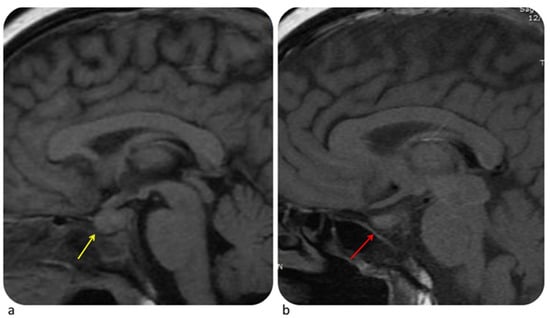

6.4.1. Pituitary Gland